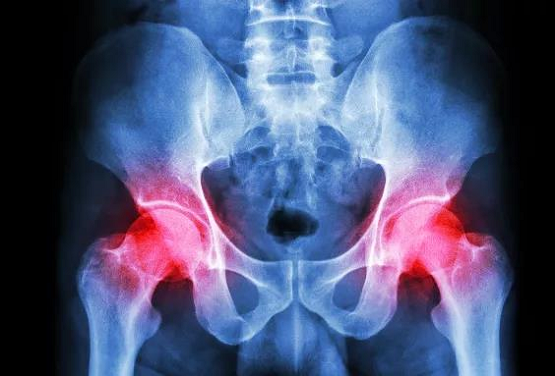

导语:股骨头缺血性坏死(ONFH)是各种原因导致股骨头内淤血或血供障碍,骨细胞及骨髓成分发生坏死的病理过程,引起髋关节疼痛、功能障碍;而大量使用激素、酗酒及股骨颈骨折是其明确的诱因,可通过定期复查MRI或CT

导语:股骨头缺血性坏死(ONFH)是各种原因导致股骨头内淤血或血供障碍,骨细胞及骨髓成分发生坏死的病理过程,引起髋关节疼痛、功能障碍;而大量使用激素、酗酒及股骨颈骨折是其明确的诱因,可通过定期复查MRI或CT,及早发现股骨头坏死。一旦确诊,及早开始中医药辨证治疗和保护性负重可以避免人工关节置换手术,保住自身髋关节。

随着MRI成像的广泛普及,其对坏死组织有了更高分辨率及多平面征象,更好地显示软骨、软骨下骨、骨组织等组织结构受损情况,目前已成为准确诊断股骨头坏死的常用的检查方法以及黄金标准。若早期就被查出股骨头坏死,要尽早配合治疗,优先保髋,避免股骨头置换。